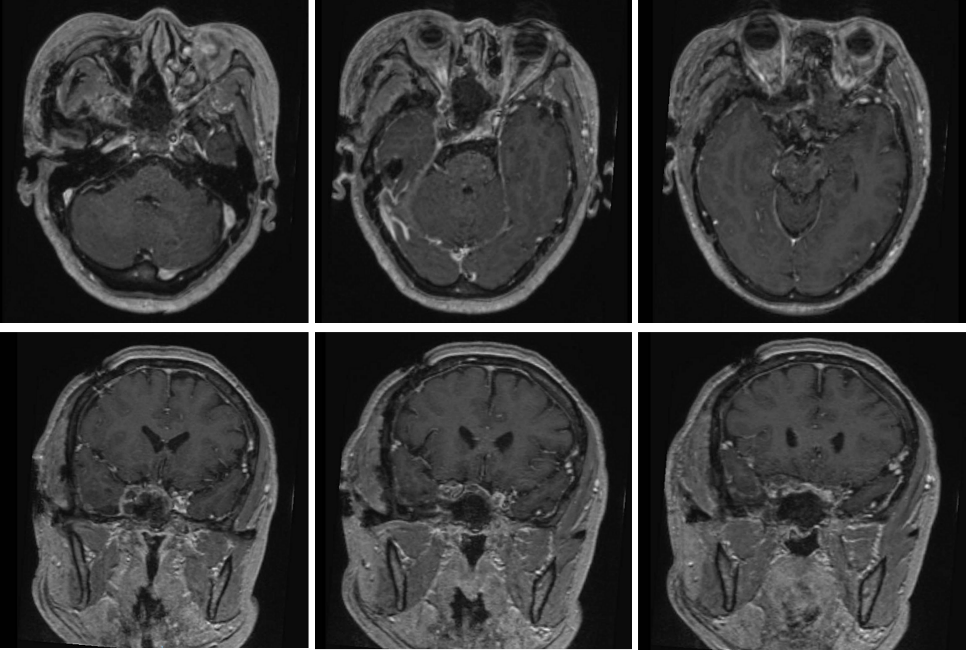

王女士因垂体瘤分别于2007年和2017年两次在外院由北京专家进行经鼻垂体瘤手术,2017年因肿瘤侵袭海绵窦未能全切,术后行伽玛刀治疗。近一个月,王女士开始出现右眼视力下降的情况,并且伴有头痛。王女士在其他医院进行头部MRI检查,显示垂体瘤复发,已广泛侵袭海绵窦并包绕颈内动脉,Knosp分级达到4级!

3月20日,吉大三院副院长、神经外科主任高宇飞教授,副主任医师赵航带领神经外科颅底疾病诊疗团队,在神经导航引导、双镜辅助下,经颅入路和经鼻入路联合进行复发侵袭海绵窦Knosp 4级垂体瘤切除术。首先,在神经内镜下经鼻手术,采用经筛翼蝶入路,切除蝶窦、筛窦、鞍内、海绵窦内的大部分肿瘤,显露颈内海绵窦段并加以保护。 然后开颅采用经典的Dolence入路,在3D外视镜下,切除海绵窦内颈内动脉外侧间隙和上间隙的残余肿瘤。

在麻醉科和手术室精心配合下,经过近6个小时的奋战,手术顺利完成,肿瘤全部切除。术中颈内动脉海绵窦段达到360度的显露,在可视下得到完好保护;术后第2日患者正常饮食,无任何神经功能损伤及活动障碍。手术取得圆满成功!